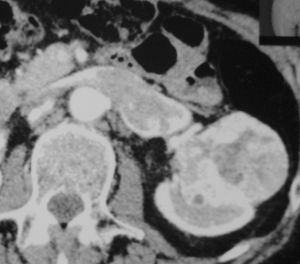

У пациентки 64 лет удалили левую почку, пораженную опухолью. Опухолевый тромб полностью заполнял почечную вену и выходил в нижнюю полую вену.

Очень нечастый клиничеcкий случай.